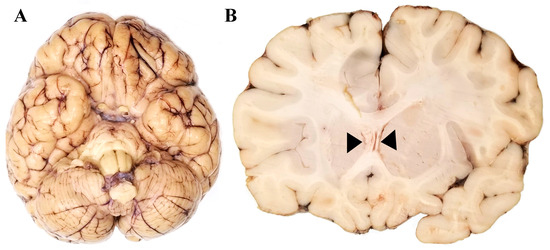

3.1. Neuropathology